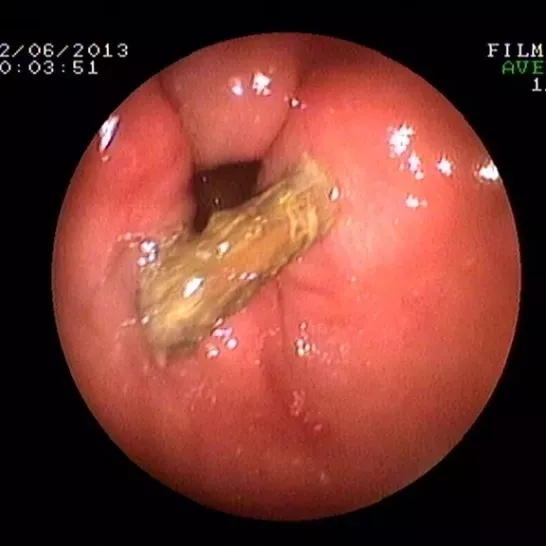

小编再带您看看这些年我院胃肠镜室从孩子身体里取出过的异物,对照一下,您家孩子接触过几样?

枣核